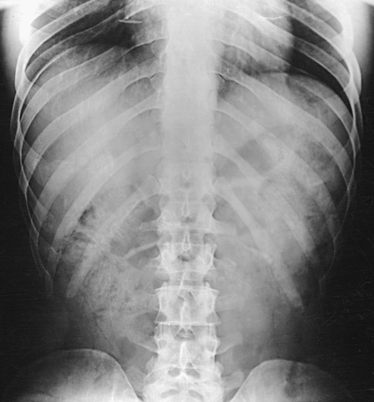

The position of the diaphragm varies with body habitus: It is at a higher level in hypersthenic patients and at a lower level in asthenic patients (Fig. 9-9). In sthenic patients of average size and shape, the right side of the diaphragm arches posteriorly from the level of about the 6th or 7th costal cartilage to the level of the 9th or 10th thoracic vertebra when the body is in the upright position. The left side of the diaphragm lies at a slightly lower level. Because of the oblique location of the ribs and the diaphragm, several pairs of ribs appear on radiographs to lie partly above and partly below the diaphragm.

Fig. 9-9 Diaphragm position and body habitus. A, A hypersthenic patient has a diaphragm positioned higher. B, An asthenic patient has a diaphragm positioned lower. C, Chest radiograph of a hypersthenic patient. D, Chest radiograph of an asthenic patient. Note position of diaphragm on these extremely different body types.